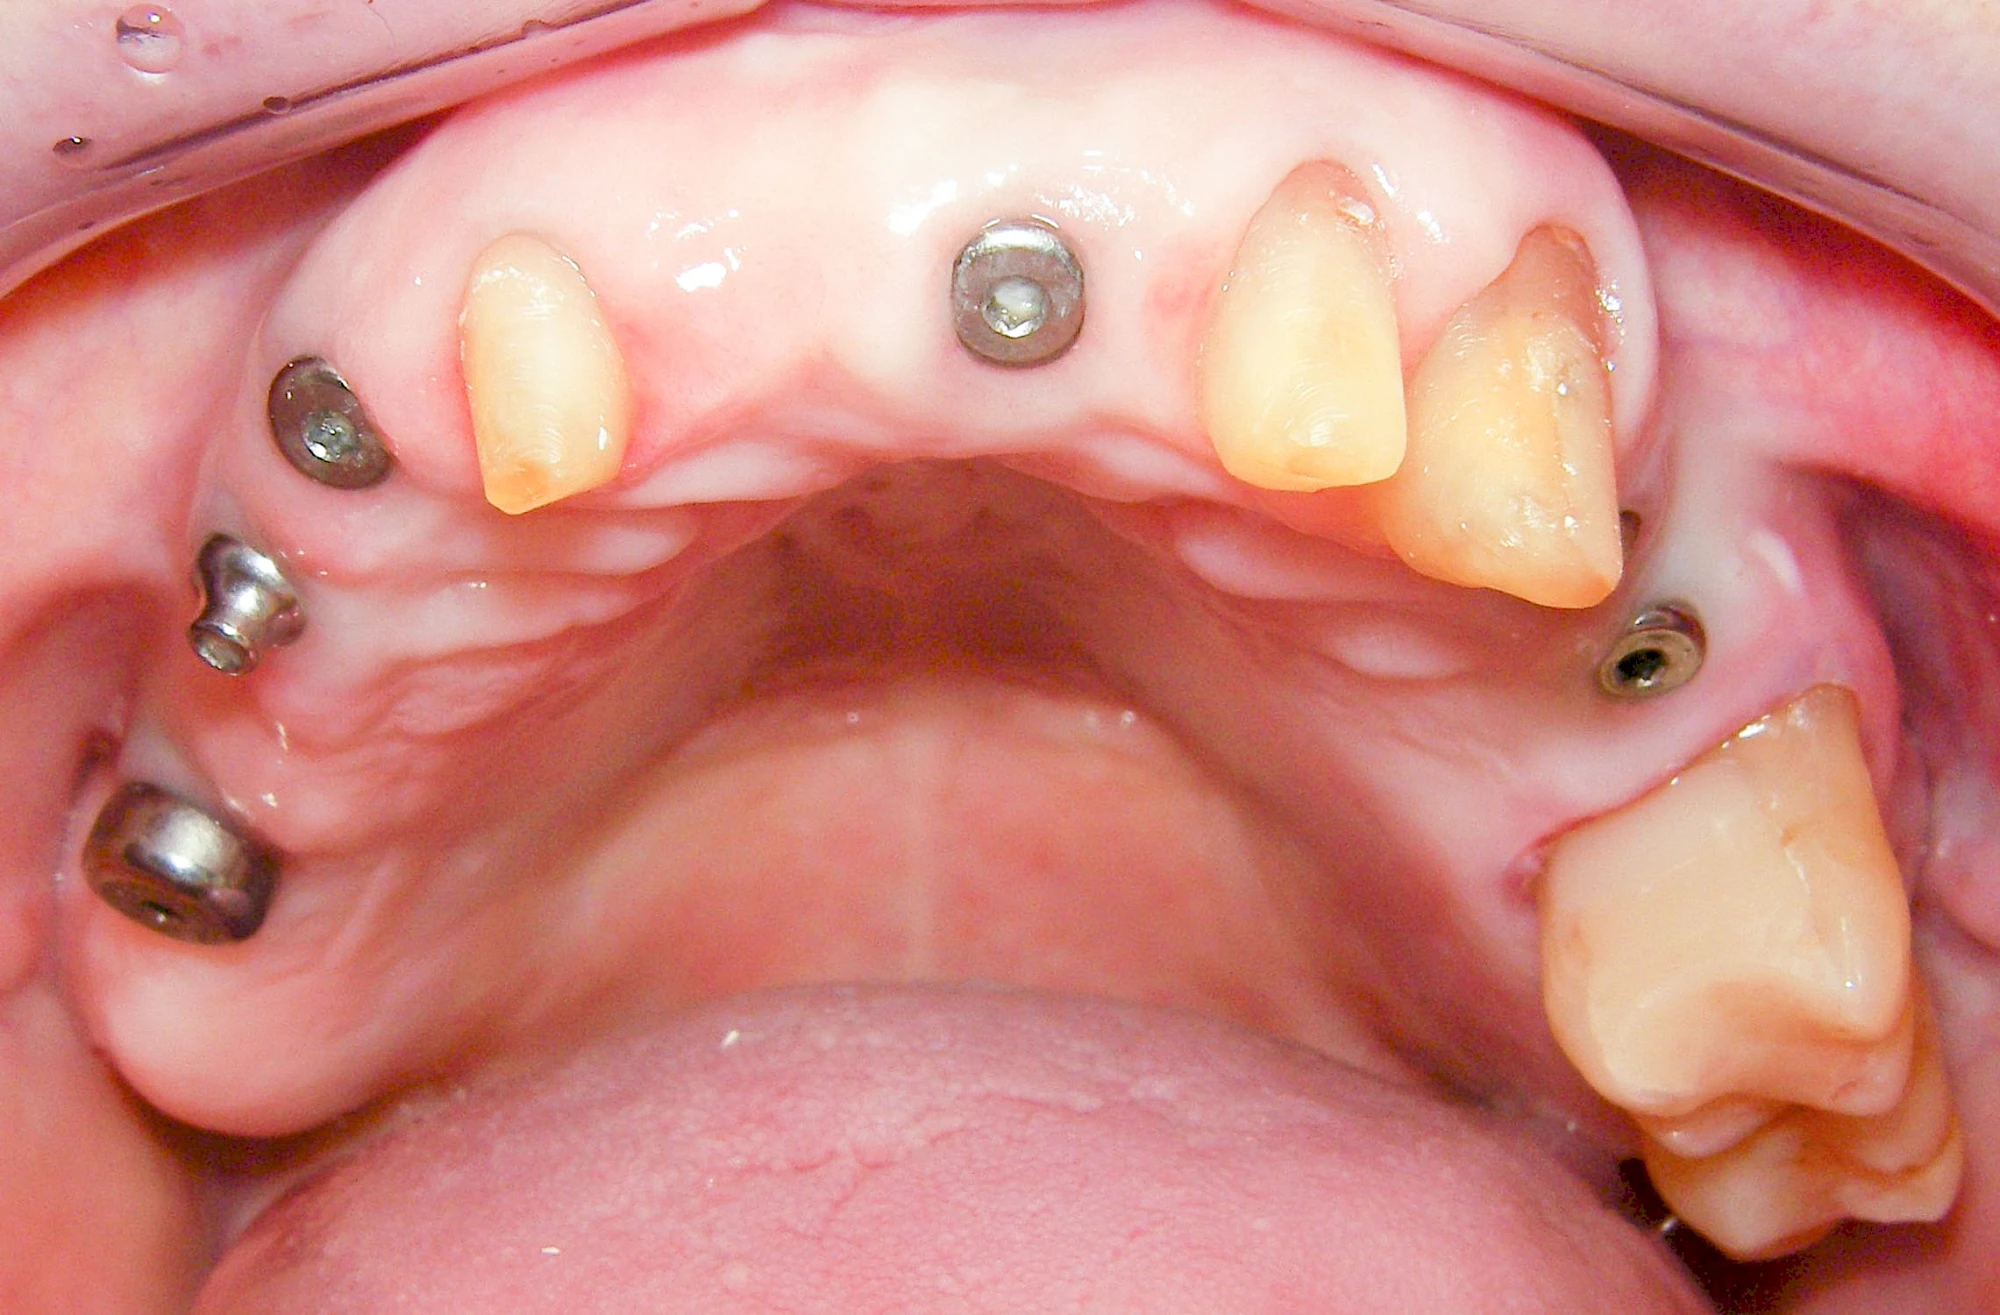

Implantate sind künstliche Zahnwurzeln. Nach einer gewissen Einheilzeit im Knochen (meist 3-6 Monate) erfolgt über einen separaten Aufbau (Abutment) die Befestigung einer Krone bzw. Brücke oder Zahnprothese.

In seltenen Fällen sind Implantate samt Aufbau aus einem Stück gefertigt. Auch gibt es Situationen, die ein Früh- oder sogar eine Sofortbelastung erlauben – dann kann die Einheilzeit der Implantate in den Knochen verkürzt oder sogar gänzlich darauf verzichtet werden.

Fehlen einzelne Zähne und die Nachbarzähne sind unbeschadet oder gut zahnärztlich versorgt, werden immer häufiger Implantate gewählt, um die Lücken zu schließen. Auch bei größeren oder verteilten Lücken, wenn keine herausnehmbare Prothese gewünscht ist, werden Implantate für Kronen- bzw. Brückenversorgungen gesetzt. In Einzelfällen entscheiden sich sogar zahnlose Patienten für eine festsitzende Versorgung auf Implantaten.

Varianten zur Verankerung von festsitzendem Zahnersatz auf Implantaten

Implantatplanung

Damit Implantate an der richtigen Stelle im Kieferknochen platziert werden könen, gibt es heute vielfältige Möglichkeiten der Planung. In vielen Situationen kann die Erfahrung des Zahnarztes ausreichend sein.

Nicht selten ist jedoch auch eine technisch aufwändigere Vermessung im Vorfeld sinnvoll, z. B.:

- Wenn wenige Restzähne keine gute Orientierung erlauben

In diesen Fällen kann die Planung mittels verschieden aufwendiger Röntgen-Techniken (Übersichtsaufnahme, DVT) ggf. unter Zuhilfenahme speziell angefertigter Planungsschablonen sinnvoll sein.